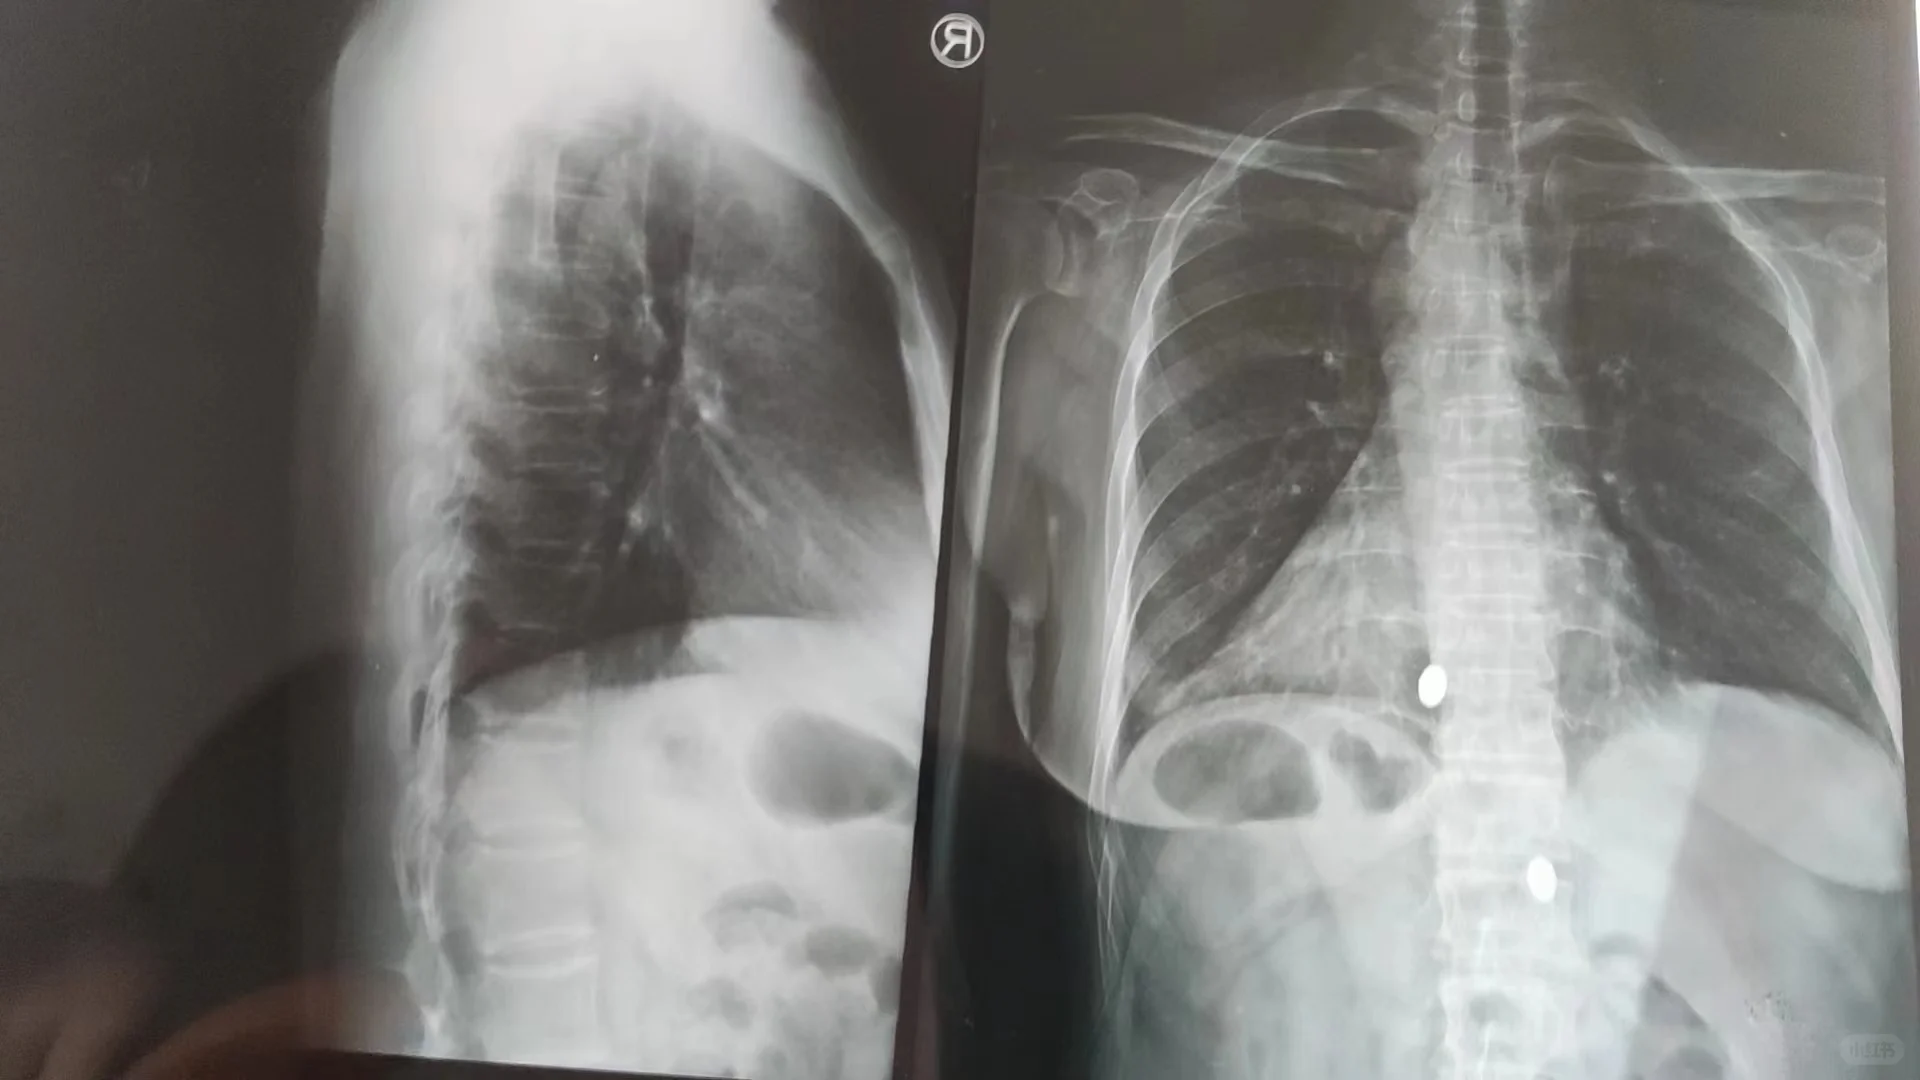

来自青岛的个案 因为右脚崴过以后右侧腿不敢吃重 身体基本靠左腿支撑 左侧肱骨半脱位 因为肱骨半脱位 导致肩胛没有向上支撑力 这时候斜方肌会用力收缩向上提 这必然导致斜方肌的紧张 她经常找人松解也无法松开 因为她斜方肌的收缩是身体的一种代偿保护机制 所以松过以后会很快就紧 另外再加上肩胛提肌也会收缩 会导致颈椎向左旋转 调整了肱骨头半脱位后 左侧斜方肌马上就松开了 原来左手不敢用力抓不起东西 调整后直接可以抓起我茶室的椅子 颈椎旋转的椎体用捶正法调整 整个颈椎就暖了 而且昨天晚上睡觉的时候 感觉到左侧头胀 头非常热 其实是因为调整了颈椎旋转后 脑供血变好头才会觉得热与胀 她平时整个颈椎都是凉的 另外胸椎段也是凉的 因为胸椎也是旋转的 还有就是她还经常头疼 感觉头顶像被保鲜膜给包着似的 其实是第一颈椎的问题 调整过第一颈椎后问题基本解除 另外是左侧咬合不舒服 调整了旋转的第二颈椎 左侧咬合明显轻松了 另外她左侧手腕也是没有力 把手腕各关节调整后 手的抓握力明显有提升 并且左侧肩也松 颈椎也觉得更轻松